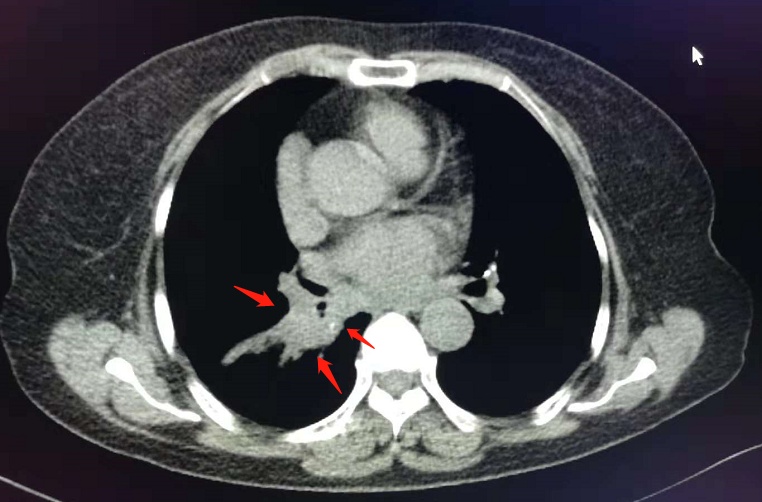

像这位病人,反复胸闷两个月,小细胞肺癌并广泛转移。

化疗两个周期后复查,病灶显著缩小: